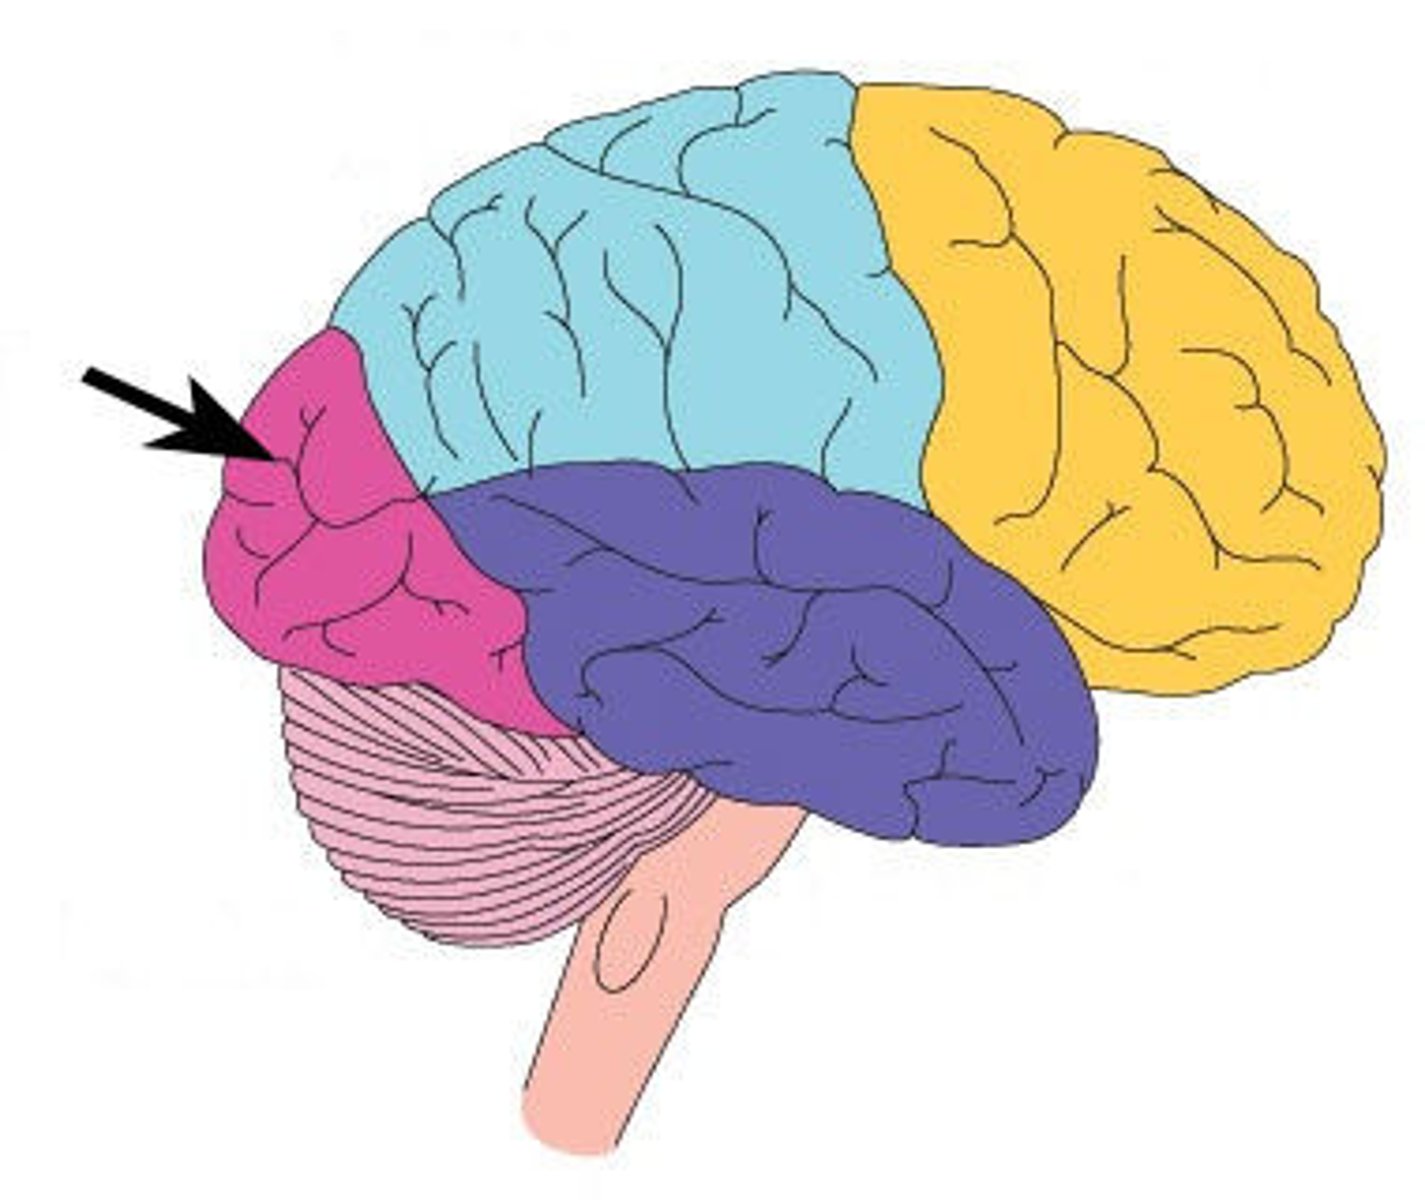

frontal lobe

parietal lobe

temporal lobe

occipital lobe

insula